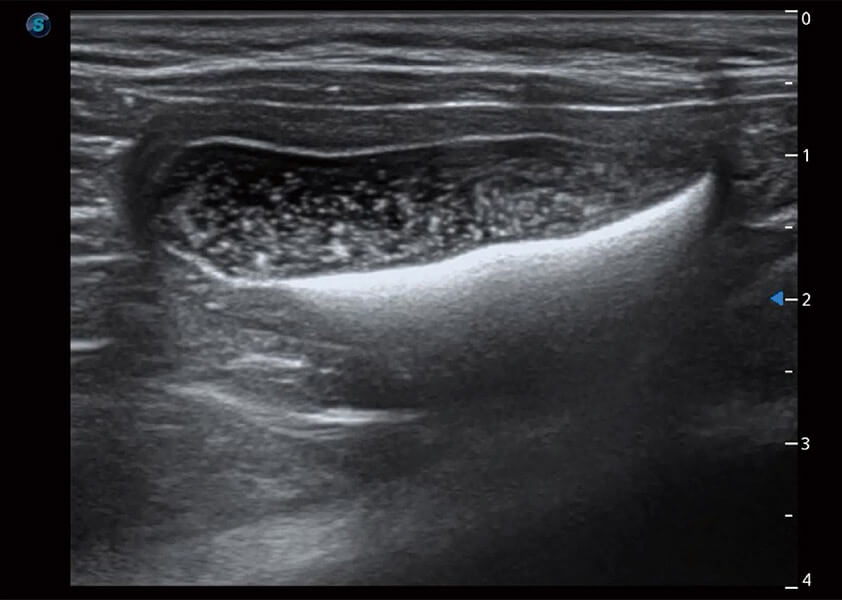

(猫)膀胱结晶